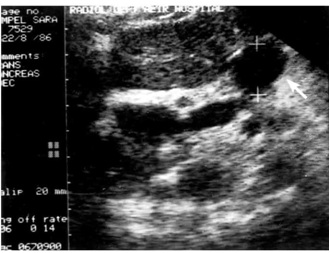

2.על-שמע (אולטרהסאונד) — בחולים הלוקים בשאתות בלבלב אפשר להדגים את השאת, וכן לראות את דרכי המרה (תצלום 23.9).

האולטרה-סאונד האנדוסקופי (EUS) מאפשרת לראות את השאת, את גודלה (איור 24.9);

האם פרצה לאיברים אחרים, תפסה כלי דם או מערבת בלוטות לימפה (תצלום 25.9).